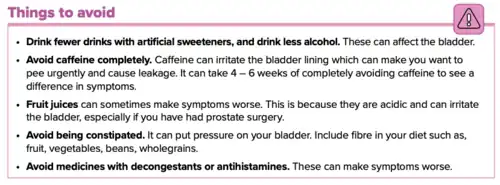

Lifestyle alterations to address the symptoms of BPH include physical activity,[59] decreasing fluid intake before bedtime, moderating the consumption of alcohol and caffeine-containing products, and following a timed voiding schedule.

Patients can also attempt to avoid products and medications with anticholinergic properties that may exacerbate urinary retention symptoms of BPH, including antihistamines, decongestants, opioids, and tricyclic antidepressants; however, changes in medications should be done with input from a medical professional.[60]

Medications

The two main medication classes for BPH management are alpha blockers and 5α-reductase inhibitors.[64]